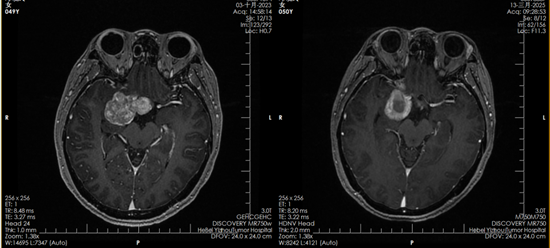

2023年10月,鄧女士正式開始質(zhì)子治療。一個多月里,她接受了30次治療。“治療的時候一點感覺都沒有,就像躺下來休息一會兒。要不是看到復查影像里的腫瘤變化,我都不敢相信這是真的。”鄧女士說。

質(zhì)子治療前后對比影像

如今,復查影像顯示腫瘤已被有效控制,她的堅持終于換來了可喜的結果。